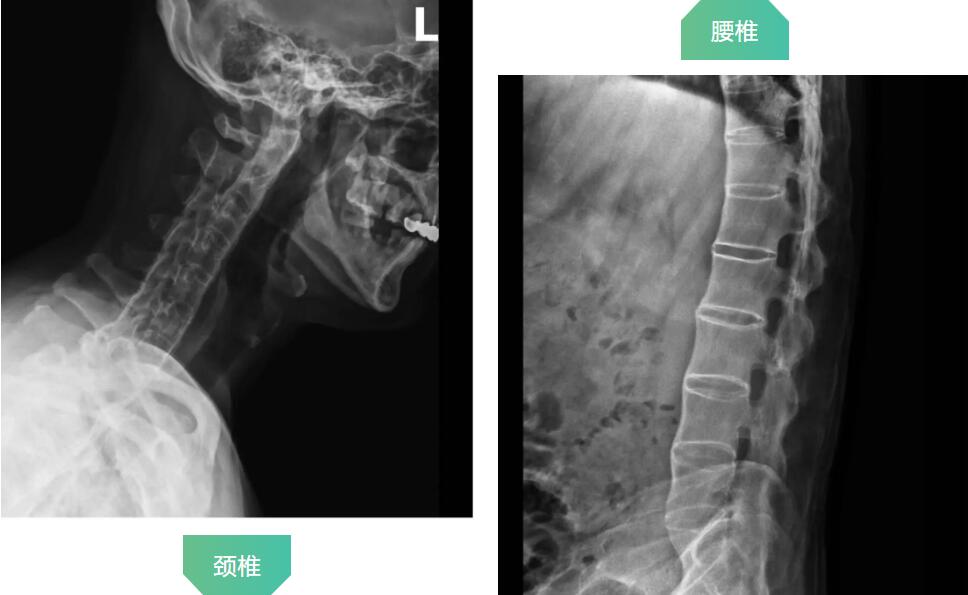

拍片顯示患者頸椎和腰椎已經(jīng)完全融合

羅軍主任分析患者病情,認(rèn)為他強(qiáng)直性脊柱炎30年,雙髖關(guān)節(jié)強(qiáng)直,骨贅增生嚴(yán)重,嚴(yán)重影響行走功能,診斷為強(qiáng)直性脊柱炎,雙側(cè)髖關(guān)節(jié)骨關(guān)節(jié)炎晚期。治療方案只有人工髖關(guān)節(jié)置換這一種選擇。因患者的頸腰椎已經(jīng)完全融合,手術(shù)和麻醉都是一個(gè)不小的挑戰(zhàn),羅軍主任帶領(lǐng)關(guān)節(jié)置換團(tuán)隊(duì)協(xié)同麻醉科團(tuán)隊(duì),經(jīng)過(guò)嚴(yán)密細(xì)致的討論,與患者及家屬充分溝通交流后,決定行機(jī)器人輔助DAA入路全髖關(guān)節(jié)置換術(shù)。機(jī)器人輔助加微創(chuàng)置換,為這項(xiàng)高難度手術(shù)提供了有力支撐。